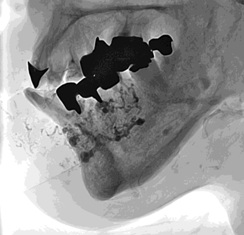

主动脉支撑架植入后II型内漏 |

选择性右髂腰动脉造影显示内漏来自于该动脉 |

右髂腰动脉NBCA栓塞术

(NBCA : Lipiodol = 1 : 4)

经肠系膜上动脉-结肠中动脉-肠系膜下动脉选择性动脉造影显示内漏还来自于该动脉 |

经微导管栓塞

(NBCA : Lipiodol = 1 :4)

NBCA 栓塞后 |